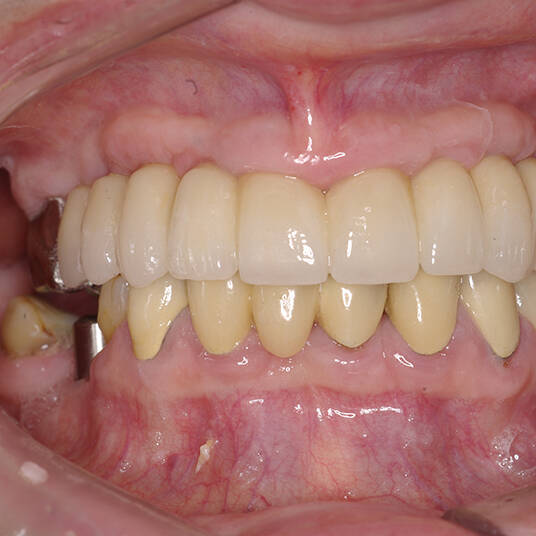

Na Clínica Pontes Odontologia, somos referência em implantes dentários em Fortaleza, oferecendo tratamentos de alta qualidade e tecnologia de ponta. Os implantes dentários são estruturas de titânio posicionadas cirurgicamente no osso maxilar ou mandibular para substituir as raízes dos dentes ausentes. Essa técnica permite a fixação de próteses personalizadas, restaurando a função mastigatória, a estética e a autoestima dos nossos pacientes.

Utilizamos a tecnologia CAD CAM, um sistema avançado que possibilita a confecção precisa das próteses dentárias diretamente sobre os implantes. Esse método inovador garante um ajuste perfeito, um resultado estético superior e proporciona muito mais conforto e durabilidade. Com o CAD CAM, nossos pacientes contam com um processo mais rápido e previsível para alcançar o sorriso desejado.

Nosso compromisso é oferecer um tratamento de excelência, com profissionais especializados e tecnologia de última geração para implantes dentários em Fortaleza. Venha nos visitar e descubra por que a Clínica Pontes Odontologia é referência em implantes dentários em Fortaleza, devolvendo sorrisos e qualidade de vida aos nossos pacientes.